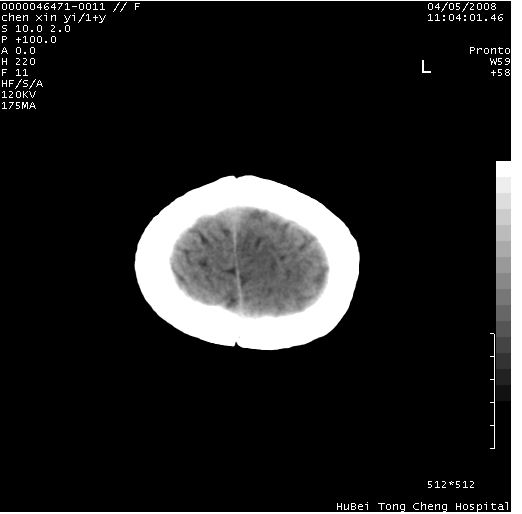

以下是引用zhangzhongshou在2008-4-9 12:54:00的发言:[br]请结合病史,有以下可能1、炎性肉芽肿钙化(含结核)2、寄生虫钙化(含脑囊虫)3、其他良性钙化性病变